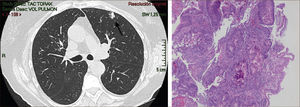

La masificación de los métodos de diagnóstico por imágenes, especialmente del TAC de Tórax, ha significado un importante aumento en la detección de NP pequeños, menores de 2cm, no visibles en la radiografía de tórax. Estos nódulos pueden ser tanto sólidos como sub-sólidos, cada uno tiene diferente comportamiento, velocidad de crecimiento y probabilidad de malignidad2,3 (Figuras 2 y 3).

El diagnóstico por imágenes mediante TAC de Tórax, cumple por tanto un rol fundamental en la identificación y caracterización de los nódulos pulmonares. Los cánceres pulmonares iniciales pueden presentarse como nódulos de diferente densidad: sólidos, cavitados, en vidrio esmerilado (VE: definidas como una intensidad discretamente mayor a la del parénquima pulmonar a través de la cual la vasculatura pulmonar es visible) o lesiones mixtas con componente sólido y VE. Figuras 2 y 33. En etapas más avanzadas los CPNCP se presentan como nódulos de mayor tamaño o masas (>3cms), sin embargo también pueden presentarse como lesiones consolidadas mal definidas, especialmente algunos adenocarcinomas productores de mucina. Estas lesiones pueden ser indistinguibles de una neumonía, pero a diferencia de estas persisten en el tiempo pese al tratamiento antibiótico 27,28.

Las lesiones Subsólidas tienen un mayor riesgo de malignidad que puede alcanzar un 18%51. Las lesiones subsólidas pueden corresponder a lesiones en Vidrio Esmerilado Puro (VE o GGO: Ground Glass Opacity) o a lesiones mixtas con un componente en VE y una zona sólida (Figuras 4, 5 y 6).

Asamura recientemente correlacionó también los hallazgos radiológicos con los histológicos en diferentes nódulos pulmonares pequeños. Las lesiones en VE puro corresponderían generalmente a Hiperplasia Adenomatosa Atípica (HAA), las lesiones mixtas (con componente en VE y sólido) a adenocarcinoma in situ y las lesiones mixtas en que el componente sólido sea mayor al 50% de la lesión corresponderían a adenocarcinomas invasores53.

Los nódulos en VE menores a 5mm generalmente corresponden a Hiperplasia Adenomatosa Atípica (HAA). Los nódulos en VE mayores pueden corresponder a HAA o Adenocarcinomas. Los CPNCP que se presentan como lesiones en VE puro (pure GGO) corresponden generalmente a adenocarcinomas in situ, adenocarcinomas tipo A en la clasificación de Noguchi54Figura 4.

Las lesiones mixtas (con componente en VE y sólido), son las que tienen la mayor probabilidad de malignidad, la que alcanza hasta un 63%51. Mientras mayor sea la proporción del componente sólido, mayor es la probabilidad de malignidad y peor el pronóstico. Estas lesiones corresponden a Adenocarcinomas micro invasores o invasores (Noguchi By C), Figura 4. Finalmente el desarrollo de un componente sólido en una lesión en VE o el aumento de la proporción del componente sólido en una lesión mixta en seguimiento indica su transformación en una lesión más agresiva50,51,53–57.